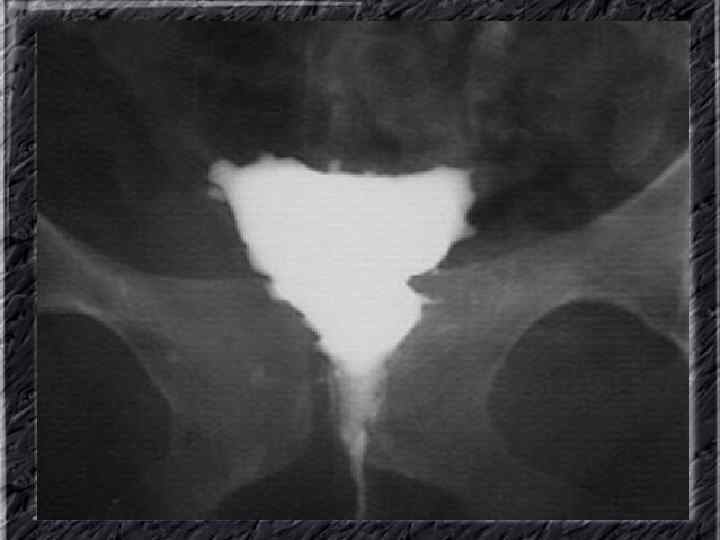

Названия слайдов: • • • Слайд 41. Лапароскопия: эндометриоидная киста яичника. Слайд 42. Лапароскопия: эндометриоидные гетеротопии на поверхности эндометриоидной кисты яичника. Слайд 43. Ультрасонография: поликистозное изменение яичника. Слайд 44. Серозная цистаденома яичника: внешний вид; макропрепарат. Слайд 45. Лапароскопия: цистаденома яичника. Слайд 46. Ультрасонография: папиллярная цистоаденома яичника, содержащая внутри папиллярные разрастания. Слайд 47. Ультраснография: многокамерная киста яичника (муцинозная цистаденома). Слайд 48. Лапароскопия: папиллярная цистаденома. Слайд 49. Ультрасонография: многокамерное жидкостное образование яичника, содержащее полиморфный солидный конгломерат — рак из муцинозной цистаденомы. Слайд 50. Рентгеноконтрастная сальпингография: нормальное наполнение и проходимость обеих маточных труб.